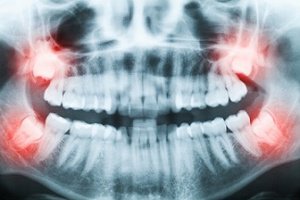

5 Things You Didn’t Know About Your Wisdom Teeth

There are lots of questions surrounding wisdom teeth, also known as third molars. While most people have wisdom teeth, they typically don’t feel them. Why is that? If you don’t feel them, why have them surgically removed? And, why are they called wisdom teeth in the first place? At Cumberland Surgical Arts, we believe in […]